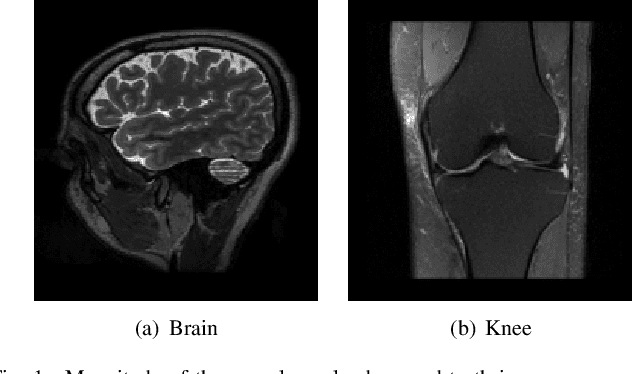

Abstract:Many inverse problems and signal processing problems involve low-rank regularizers based on the nuclear norm. Commonly, proximal gradient methods (PGM) are adopted to solve this type of non-smooth problems as they can offer fast and guaranteed convergence. However, PGM methods cannot be simply applied in settings where low-rank models are imposed locally on overlapping patches; therefore, heuristic approaches have been proposed that lack convergence guarantees. In this work we propose to replace the nuclear norm with a smooth approximation in which a Huber-type function is applied to each singular value. By providing a theoretical framework based on singular value function theory, we show that important properties can be established for the proposed regularizer, such as: convexity, differentiability, and Lipschitz continuity of the gradient. Moreover, we provide a closed-form expression for the regularizer gradient, enabling the use of standard iterative gradient-based optimization algorithms (e.g., nonlinear conjugate gradient) that can easily address the case of overlapping patches and have well-known convergence guarantees. In addition, we provide a novel step-size selection strategy based on a quadratic majorizer of the line-search function that leverages the Huber characteristics of the proposed regularizer. Finally, we assess the proposed optimization framework by providing empirical results in dynamic magnetic resonance imaging (MRI) reconstruction in the context of locally low-rank models with overlapping patches.

Abstract:In compressed sensing (CS) MRI, model-based methods are pivotal to achieving accurate reconstruction. One of the main challenges in model-based methods is finding an effective prior to describe the statistical distribution of the target image. Plug-and-Play (PnP) and REgularization by Denoising (RED) are two general frameworks that use denoisers as the prior. While PnP/RED methods with convolutional neural networks (CNNs) based denoisers outperform classical hand-crafted priors in CS MRI, their convergence theory relies on assumptions that do not hold for practical CNNs. The recently developed gradient-driven denoisers offer a framework that bridges the gap between practical performance and theoretical guarantees. However, the numerical solvers for the associated minimization problem remain slow for CS MRI reconstruction. This paper proposes a complex quasi-Newton proximal method that achieves faster convergence than existing approaches. To address the complex domain in CS MRI, we propose a modified Hessian estimation method that guarantees Hermitian positive definiteness. Furthermore, we provide a rigorous convergence analysis of the proposed method for nonconvex settings. Numerical experiments on both Cartesian and non-Cartesian sampling trajectories demonstrate the effectiveness and efficiency of our approach.

Abstract:Deep Learning (DL) methods can reconstruct highly accelerated magnetic resonance imaging (MRI) scans, but they rely on application-specific large training datasets and often generalize poorly to out-of-distribution data. Self-supervised deep learning algorithms perform scan-specific reconstructions, but still require complicated hyperparameter tuning based on the acquisition and often offer limited acceleration. This work develops a bilevel-optimized implicit neural representation (INR) approach for scan-specific MRI reconstruction. The method automatically optimizes the hyperparameters for a given acquisition protocol, enabling a tailored reconstruction without training data. The proposed algorithm uses Gaussian process regression to optimize INR hyperparameters, accommodating various acquisitions. The INR includes a trainable positional encoder for high-dimensional feature embedding and a small multilayer perceptron for decoding. The bilevel optimization is computationally efficient, requiring only a few minutes per typical 2D Cartesian scan. On scanner hardware, the subsequent scan-specific reconstruction-using offline-optimized hyperparameters-is completed within seconds and achieves improved image quality compared to previous model-based and self-supervised learning methods.

Abstract:Diffusion models have achieved excellent success in solving inverse problems due to their ability to learn strong image priors, but existing approaches require a large training dataset of images that should come from the same distribution as the test dataset. When the training and test distributions are mismatched, artifacts and hallucinations can occur in reconstructed images due to the incorrect priors. In this work, we systematically study out of distribution (OOD) problems where a known training distribution is first provided. We first study the setting where only a single measurement obtained from the unknown test distribution is available. Next we study the setting where a very small sample of data belonging to the test distribution is available, and our goal is still to reconstruct an image from a measurement that came from the test distribution. In both settings, we use a patch-based diffusion prior that learns the image distribution solely from patches. Furthermore, in the first setting, we include a self-supervised loss that helps the network output maintain consistency with the measurement. Extensive experiments show that in both settings, the patch-based method can obtain high quality image reconstructions that can outperform whole-image models and can compete with methods that have access to large in-distribution training datasets. Furthermore, we show how whole-image models are prone to memorization and overfitting, leading to artifacts in the reconstructions, while a patch-based model can resolve these issues.

Abstract:Diffusion models can learn strong image priors from underlying data distribution and use them to solve inverse problems, but the training process is computationally expensive and requires lots of data. Such bottlenecks prevent most existing works from being feasible for high-dimensional and high-resolution data such as 3D images. This paper proposes a method to learn an efficient data prior for the entire image by training diffusion models only on patches of images. Specifically, we propose a patch-based position-aware diffusion inverse solver, called PaDIS, where we obtain the score function of the whole image through scores of patches and their positional encoding and utilize this as the prior for solving inverse problems. First of all, we show that this diffusion model achieves an improved memory efficiency and data efficiency while still maintaining the capability to generate entire images via positional encoding. Additionally, the proposed PaDIS model is highly flexible and can be plugged in with different diffusion inverse solvers (DIS). We demonstrate that the proposed PaDIS approach enables solving various inverse problems in both natural and medical image domains, including CT reconstruction, deblurring, and superresolution, given only patch-based priors. Notably, PaDIS outperforms previous DIS methods trained on entire image priors in the case of limited training data, demonstrating the data efficiency of our proposed approach by learning patch-based prior.